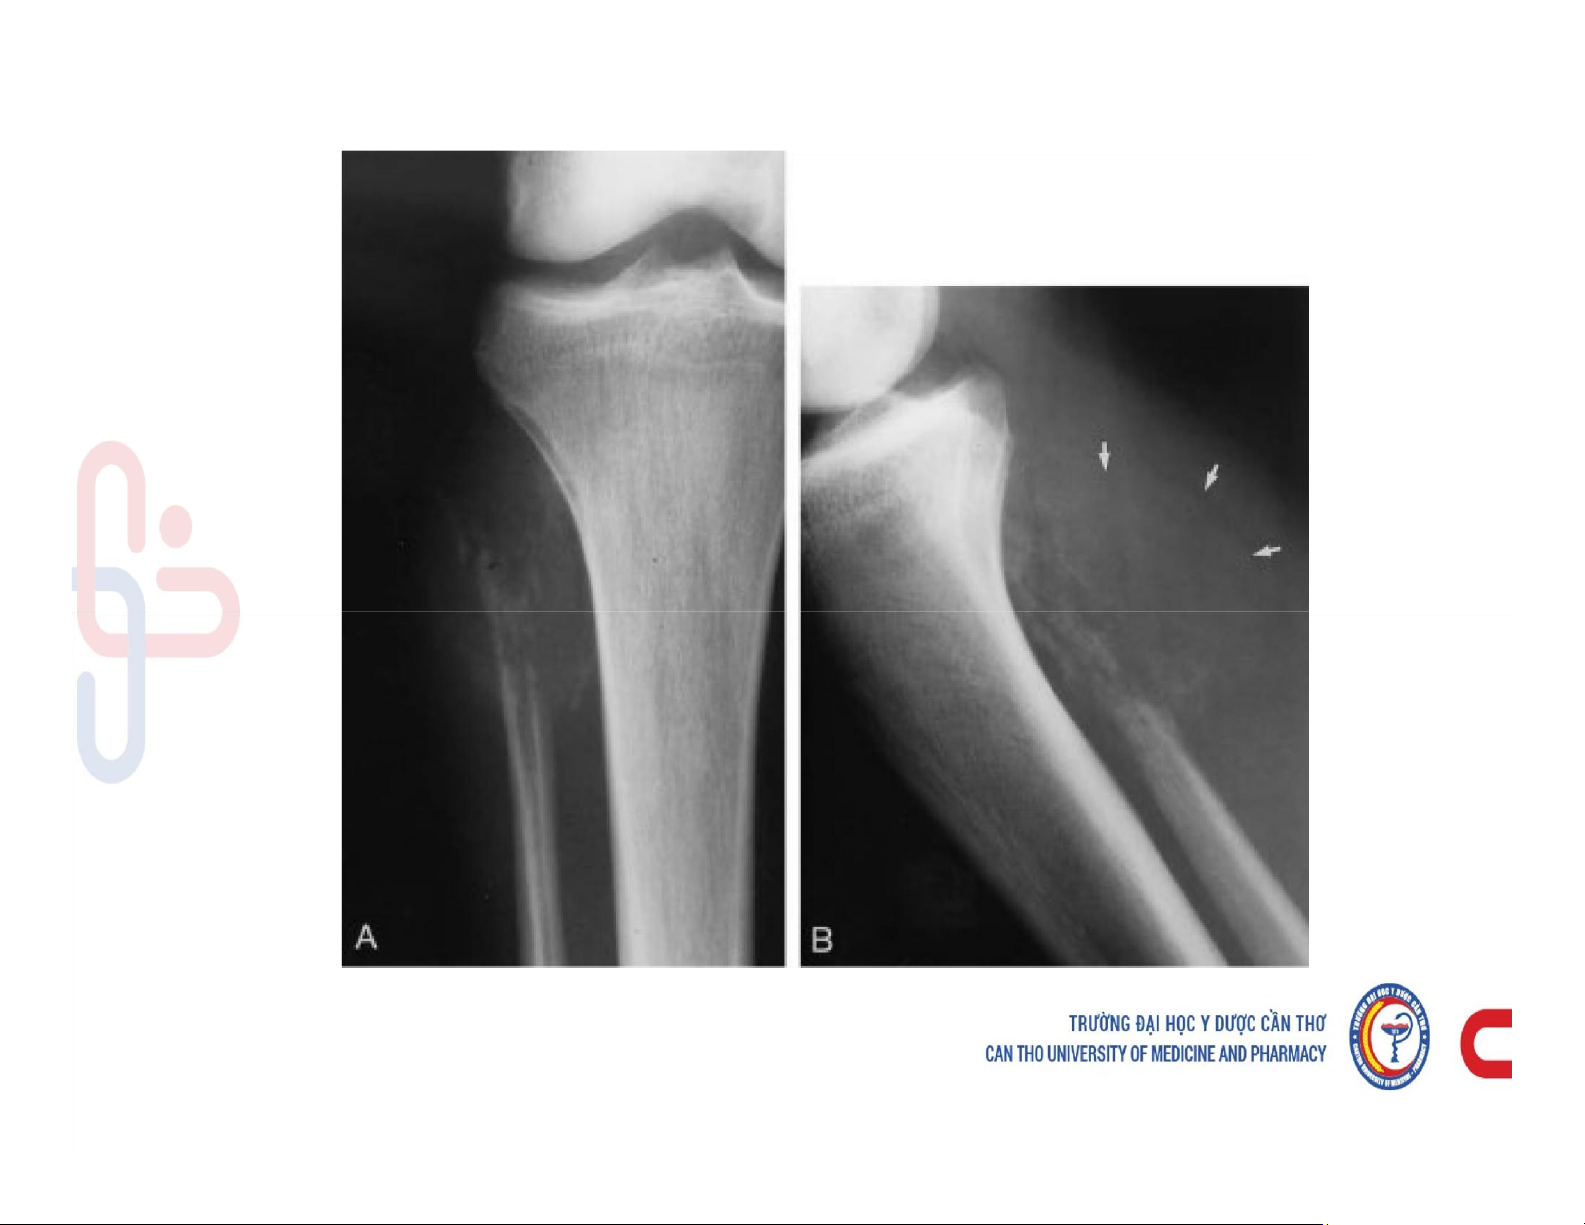

Mô tả và chú thích được các cấu trúc giải phẫu x quang xương khớp. Mô tả các dấu hiệu cơ bản trên phim x quang xương khớp. Phân tích được hình ảnh x quang bệnh lý của một số nhóm bệnh lý xương khớp. Các dấu hiệu cơ bản của phim. Tài liệu giúp bạn tham khảo, ôn tập và đạt kết quả cao. Mời đọc đón xem!